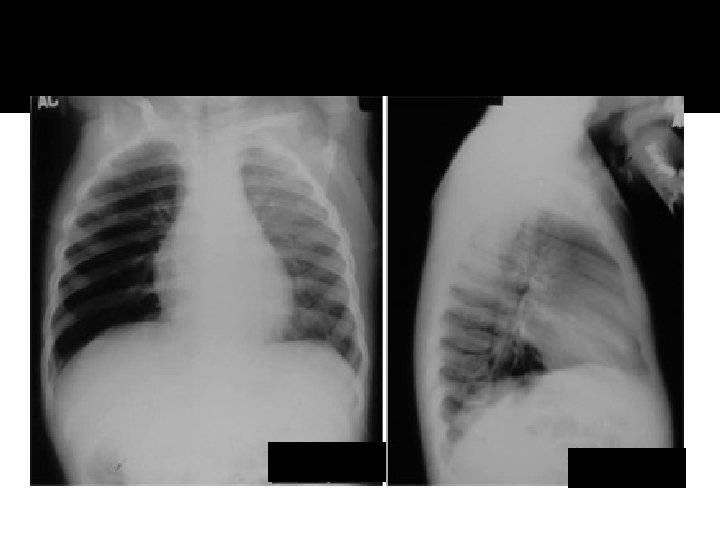

Atelectasis RML

Pneumonia lingula

Atelecasis RML